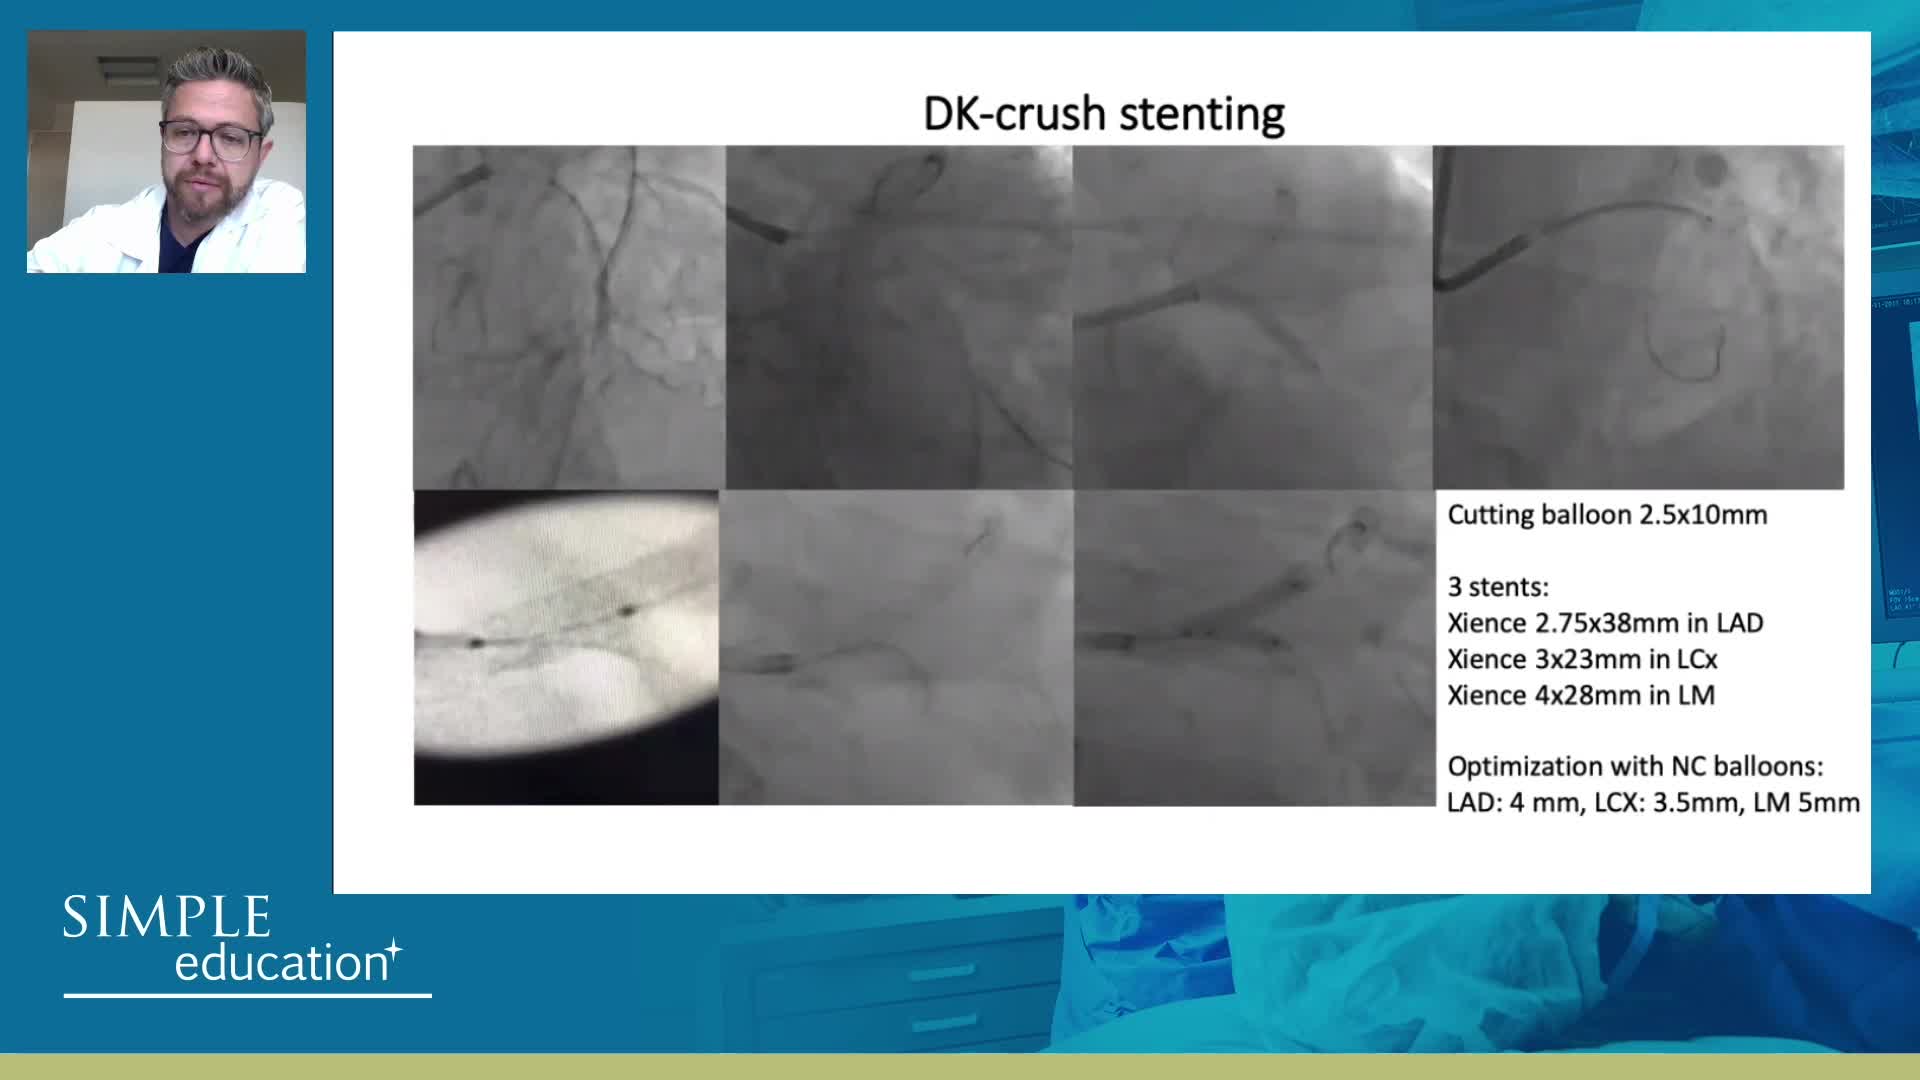

Coronary Bifurcations: An Update on Diagnosis, PCI planning and Imaging and PhysiologyGuidance - Dr Dejan Milasinovic

Best practices and personalised medicine in complex PCI - Prof Javier Escaned

Essential steps for physiology-based PCI planning and guidance - Dr Allen Jeremias